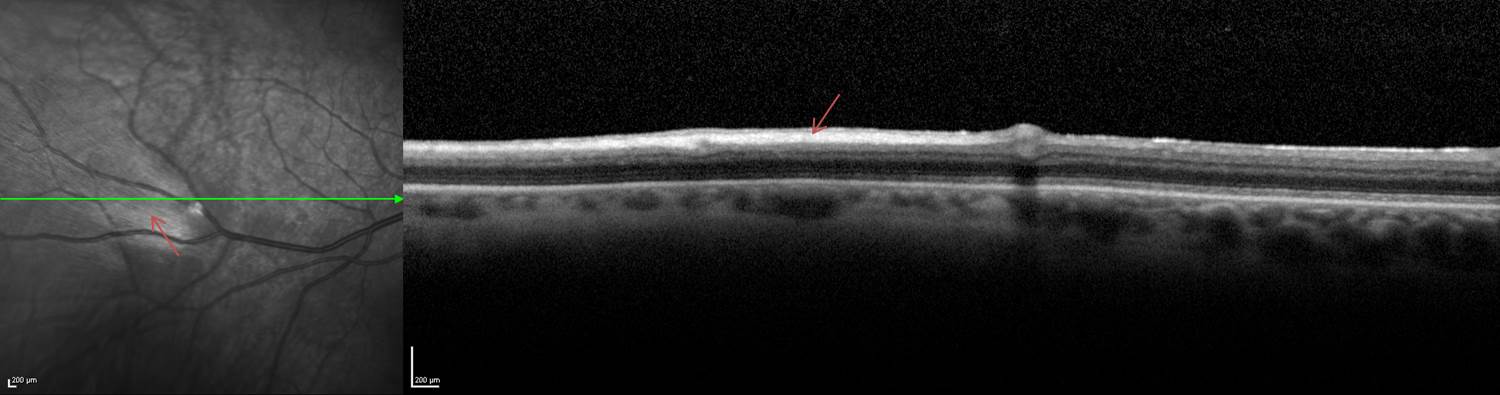

On infrared and red-free imaging, MRNF appears white, which is likely due to the high lipid content of myelin.[25] Myelin blocks detection of underlying fluorescent material, thus appearing dark on fundus autofluorescence (FAF). On optical coherence tomography (OCT), MRNF appears as a thickened and hyperreflective retinal nerve fiber layer (RNFL) (Figure 2).

Figure 2. OCT in which red arrows identify the hyperreflective appearance of a myelinated retinal nerve fiber layer.